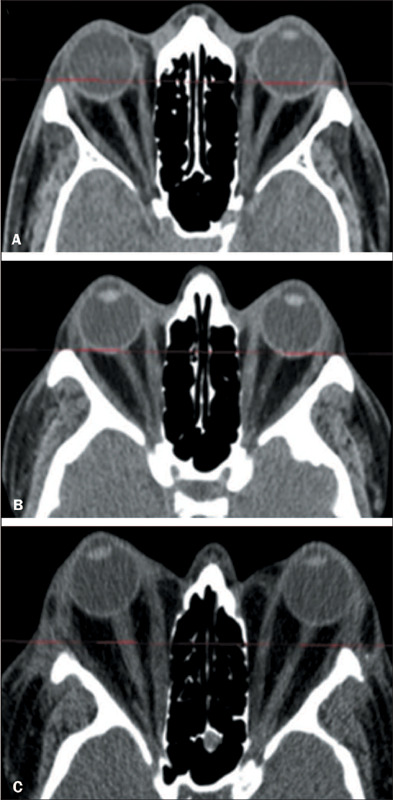

Objective: To assess the prevalence of changes on computed tomography (CT) in Graves' orbitopathy (GO) and to correlate those changes with disease activity, as well as with clinical and biochemical variables.

Materials and methods: This was a retrospective study, conducted at a tertiary hospital, of clinical, biochemical, and imaging data from consecutive patients with GO who underwent at least one orbital CT scan between July 2012 and December 2020. A single observer quantified the thickness of the extraocular muscles and the degree of proptosis. Clinical and biochemical variables were analyzed to determine whether they correlated with CT changes, GO activity, and GO severity.

Results: Our sample included data from 67 patients with GO (134 orbits), 50 (74.6%) of whom were female. There were positive correlations between the clinical activity score and increase in thyroid-stimulating factor/free thyroxine, between the severity of GO and the increase in the thickness of the extraocular muscles, and between the degree of proptosis and muscle thickness.

Conclusion: Orbital CT proved effective in detecting thickening of the extraocular muscles and proptosis in patients with GO, changes that correlated significantly with clinical and biochemical variables. Muscle thickening was associated with the severity of GO and could be a biomarker of the risk of vision loss.